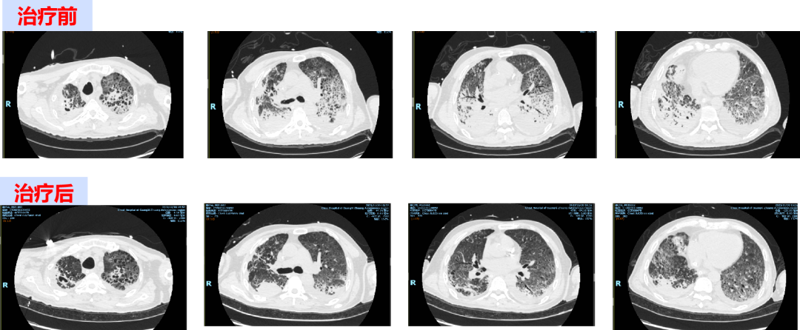

经检查,这名患者新冠病毒核酸阳性,同时合并有肺结核、肺部细菌及真菌感染,“白肺”范围达到80%,氧合指数持续小于100mmHg(正常人>400mmHg)。单纯靠常规呼吸机支持呼吸等救治手段不足以维持患者对氧供的需求,患者甚至出现了严重的心功能不全、严重低血压,经联合使用多种强心药、升压药物仍不能有效改善心功能及维持血压,情况非常危急。

经过11天的不懈奋战,患者肺部氧合改善、心功能改善、血压稳定,最终顺利撤离ECMO生命支持。此次ECMO成功撤机标志着我院危重传染病救治水平迈上一个更高的台阶,随着ECMO技术的成熟运用,能为更多重症患者带来“生”的希望,创造更多生命奇迹。